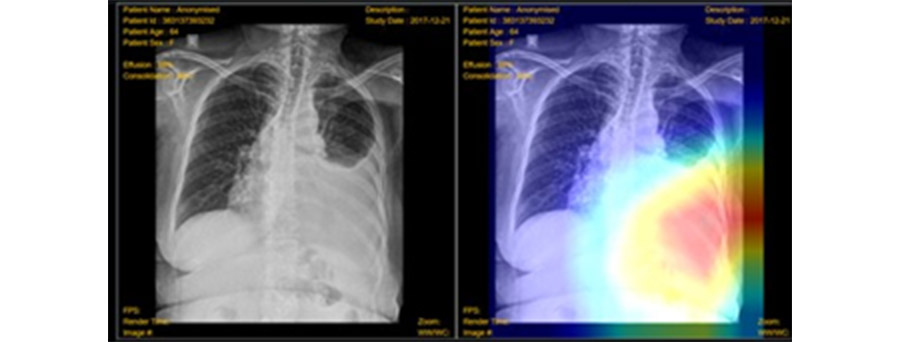

Fig. 3: Screen of AI Diagnostic Imaging Solution